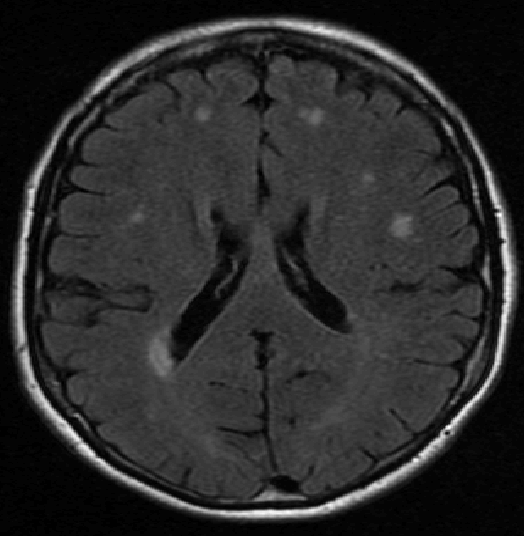

We use images from three different studies (see Fig. 1 for examples of slices):

10 MS patients from the MS Lesion Challenge [11] scanned at the Children’s Hospital of Boston (CHB), scanned with T1, T2 and FLAIR at 0.50.50.5mm resolution.

10 MS patients from the MS Lesion Challenge [11] scanned at the University of North Carolina (UNC), scanned with T1, T2 and FLAIR at 0.50.50.5mm resolution.

- 3.

Here again the differences between study populations influence the class priors. On average, the percentage of voxels that are lesions are 1.6%, 2.6% and 0.2% in CHB, RSS and UNC respectively. The differences between subjects also vary: these are relatively small for CHB and UNC, but very large for RSS. In RSS, the subject with the least lesion voxels has only 0.08%, while the patient with the most lesion voxels has 14.3%.